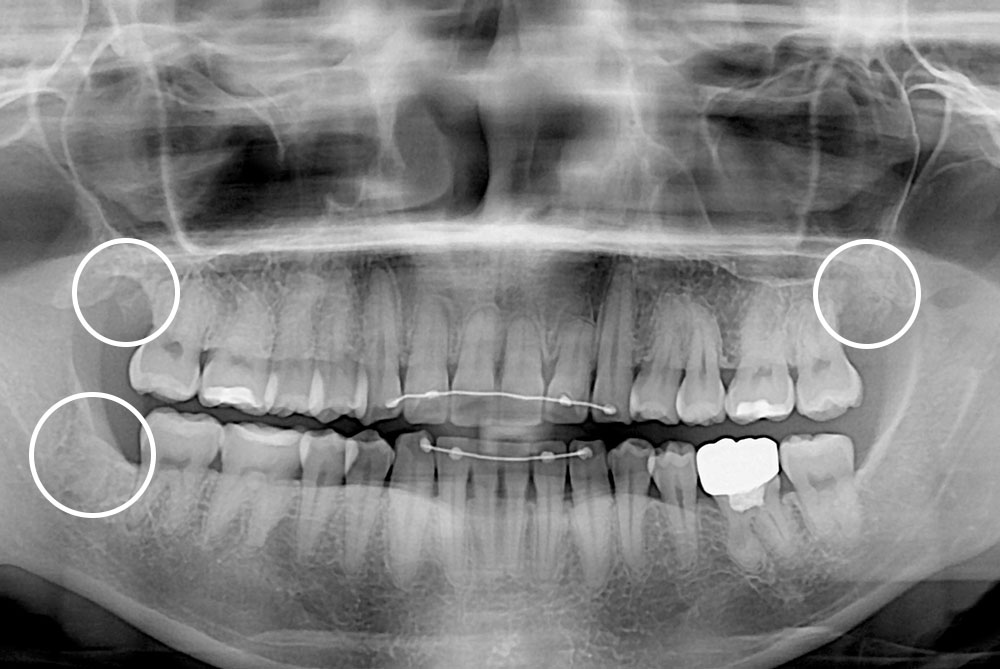

[사랑니] 매복 사랑니 발치

치료후 : 2019-10-15

세종치과는 구강악안면외과학 박사이신 원장님이 발치하는 치과입니다.